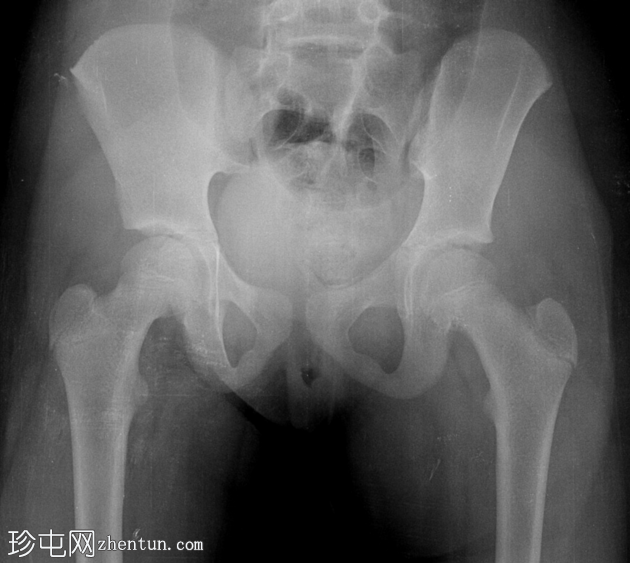

X线片

1.png

左侧髋关节后脱位。

左侧股骨头与髋臼缘重叠。

左大腿内收。

无骨折迹象。